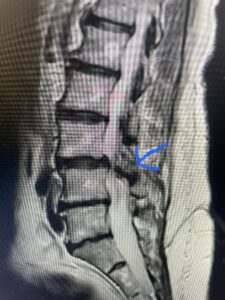

Another patient is a 62 year-old female with progressive low back pain and right leg pain and numbness that radiates to the top of her foot. She tried physical therapy and epidural injections. MRI demonstrated severe L3-4 stenosis and a grade 1 spondylolisthesis (Fig 4). There was L5-S1 and L4-5 disc collapse with modic end-plate changes. Biomechanically because of the significant degeneration of these disc spaces which stiffened the L4-S1 segment more stress was placed on the L3-4 segment, resulting in significant premature degeneration and compensatory stenosis and segmental instability. The MRI also showed pathologically, because of the slip, the L3 inferior processes were more anteriorly oriented and hence contributing to the majority of the lumbar canal compromise. Note the more sagittally-oriented facets in this case compared to the prior case (Fig 5). The patient underwent a decompressive laminectomy with attention of removing the inferior processes of L3 to fully decompress the canal. We also performed an L3-4 fusion with instrumentation (Fig 6). The patient had an uneventful postoperative course with improvement of leg pain. Of note with relief of the disabling leg pain patients are generally very happy. Patients can often manage their low back pain; it is the leg pain that they just can’t tolerate.

Fig 5 Axial T2-weighted lumbar MRI demonstrating significant L3 inferior facet contribution of severe stenosis (blue arrow)